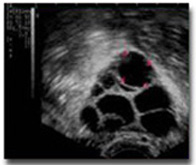

TV USG is started on day 1,2 or 3 and then from day 9 onwards, every alternate

day, until ovulation. As the ultrasound waves strike the tissues, they project

a white image on the ultrasound screen. Follicles are round sacs of fluid

within the ovaries. Therefore, the follicles appear as dark circles on the

ultrasound screen. Each follicle contains an egg; however, the eggs cannot be

seen during the ultrasound. Ovulation, if occurring, would take place usually

by day 14 – 18. On an average, 5-6 visits are required to complete an

evaluation.